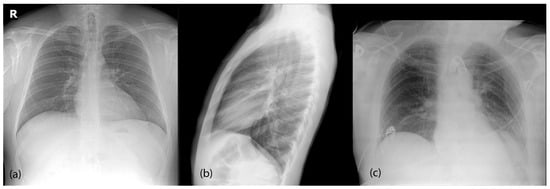

- Projections: We correctly handled data projections and corrected some labelling errors for specific images, especially in pneumothorax-positive images.